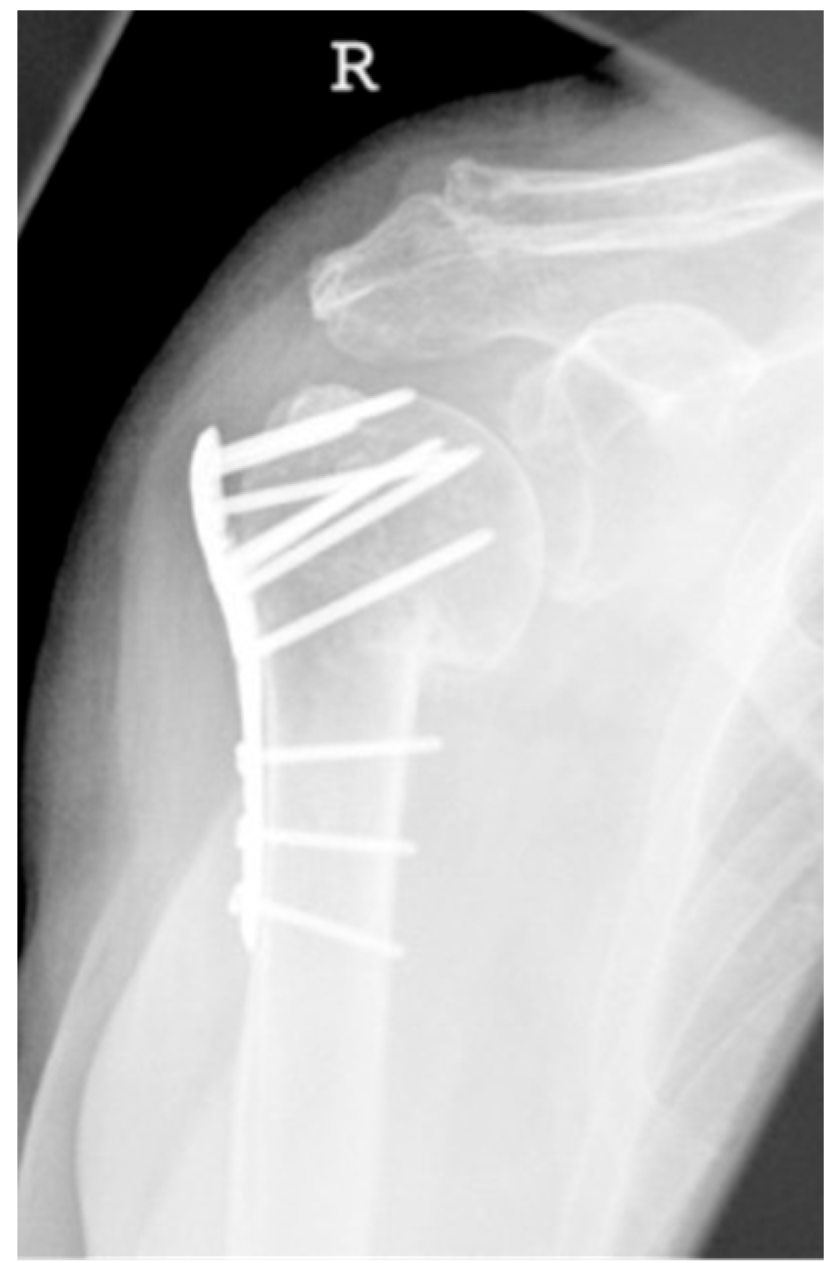

| 3 | ![]() | Type 3 describes a displacement of the angular stable plate osteosynthesis with screw cutout/fracture avulsion in the humeral shaft region, while the humeral head position remains intact. |